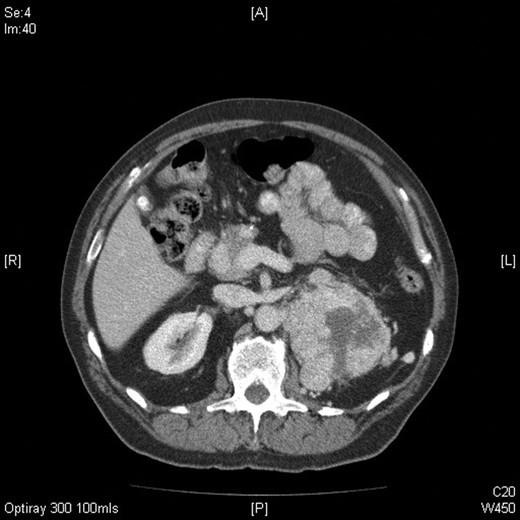

Repeat radiographs performed by his general practitioner 19 months after initial presentation (Figs 4–6) revealed a large lucency within the patella and a discontinuity in the anterior cortex of the inferior pole suggesting pathological fracture. A bone scan was arranged and demonstrated isolated abnormal tracer activity around the left patella (Fig. 7). Due to the pacemaker a computed tomography (CT) scan was performed to further characterize the lesion. This confirmed a large lucent area occupying most of the patella with multiple areas of cortical disruption along its anterior border (Fig. 8). Since the exact nature of the lesion could not be determined an ultrasound-guided biopsy was suggested but ultrasound screening revealed the lesion to be highly vascular (Fig. 9). In view of this the radiologist performed a renal ultrasound, which revealed a large mass arising from the superior pole of the left kidney. Subsequent CT of the chest, abdomen and pelvis followed demonstrating the extent of disease. There was a large (13 × 8.5 × 9 cm) mass arising from the superior pole of the left kidney (Fig. 10), the appearances of which were consistent with a primary RCC. Metastases were found in both adrenals and lungs, but no other bone metastases. Since diagnosis, the patient has had a left nephrectomy and is currently receiving radiotherapy and zolendronic acid treatment for the patella metastasis. At the time of writing this report the patient's patella lesion continues to be managed non-operatively.

Axial CT image of the abdomen confirming the presence of a large mass arising from the superior pole of the left kidney measuring 13 (craniocaudal) × 8.5 (side to side) × 9 (AP) cm with central areas of necrosis.